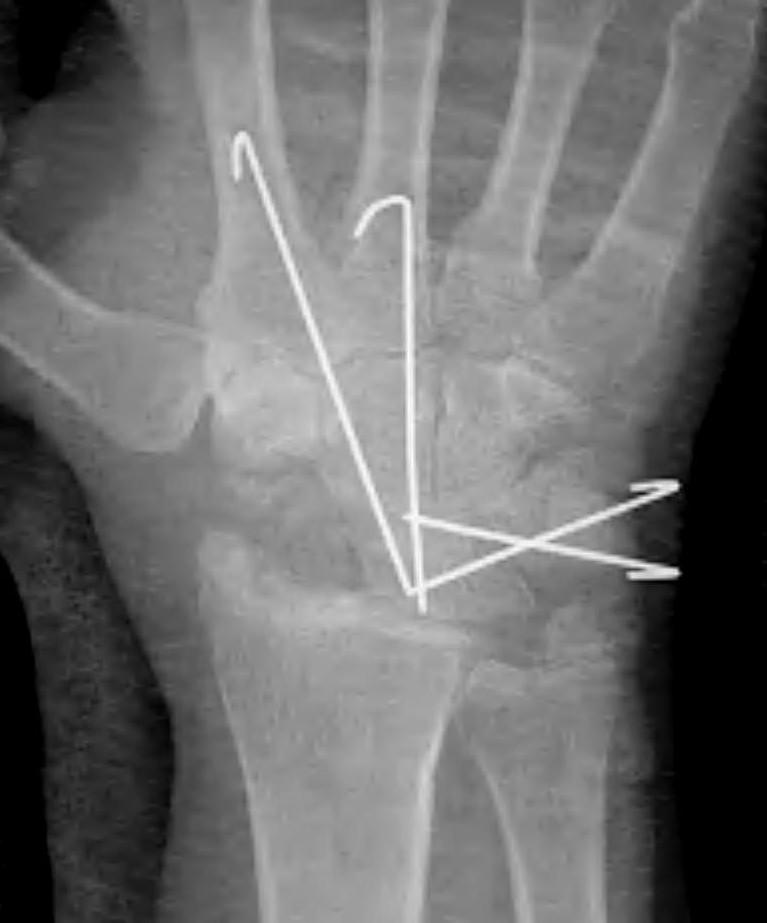

Fixation options

K wires

Headless compression screws

Dorsal locking plates

Staples

4 corner fusion techniques

4 corner: capitate / lunate screw + triquetrum / hamate / capitate screw

Bi-column: capitate / lunate screw + triquetrum / hamate screw